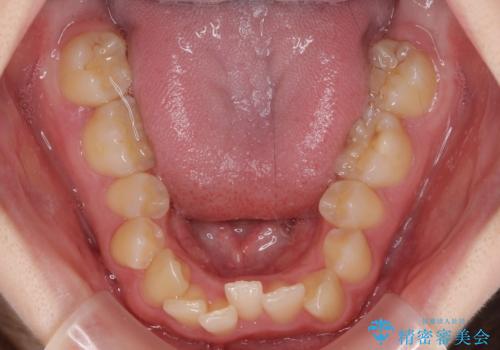

カリエールディスタライザーやワイヤー矯正を併用したことで、確実かつ短期間で治療を終えることができました。